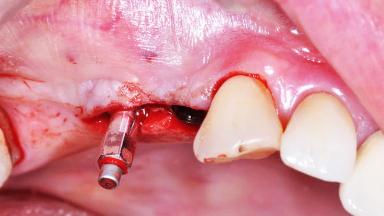

Surgical treatment of a 68-year-old female patient who experienced failure of her conventional bridge in the right maxilla. After removal of the compromised abutment teeth and a healing period of 6 weeks, a sinus floor elevation procedure using the lateral window technique and a composite graft to correct the insufficient bone height is carried out.

Two dental implants are placed in the same surgical session. The case concludes with the presentation of the final fixed dental prosthesis with a distal cantilever unit.

Bone Augmentation Simultaneous|Sinus Floor Elevation

Augmentation Materials Autogenous chips|Xenogenous